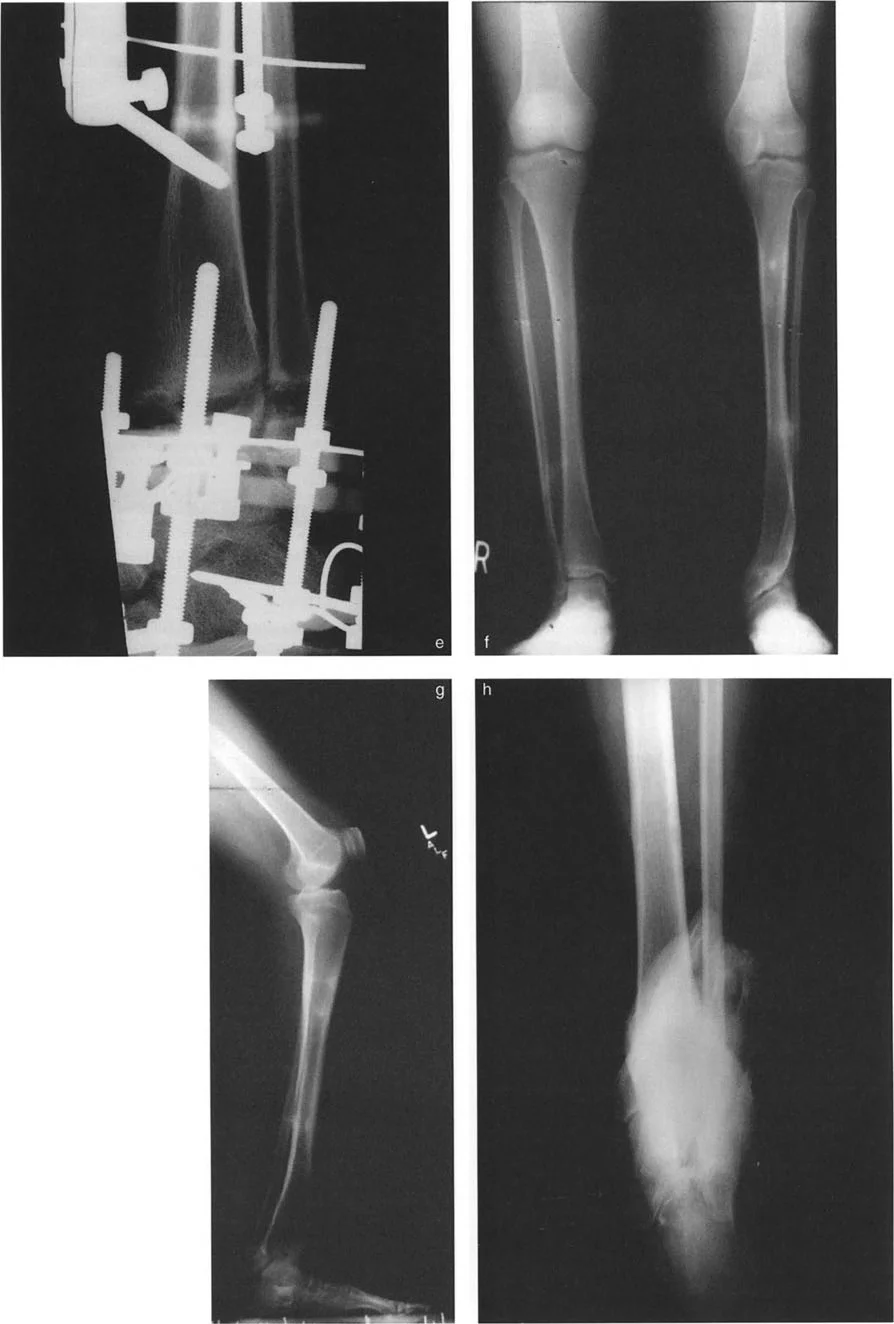

أنواع جراحات قطع العظم فوق الكاحل (Supramalleolar Osteotomy)

جراحة قطع العظم فوق الكاحل (SMO) هي الإجراء الأكثر شيوعًا لتصحيح تشوهات قصبة الساق البعيدة. تتضمن هذه الجراحة قطعًا دقيقًا في عظم الساق (القصبة) فوق مفصل الكاحل مباشرة، ثم إعادة محاذاة العظم وتثبيته في الوضع الصحيح. هناك عدة أنواع من هذه الجراحة:

صورة طبية: الاستاذ الدكتور محمد هطيف: دليل شامل لتشوهات قصبة الساق البعيدة والكاحل في صنعاء